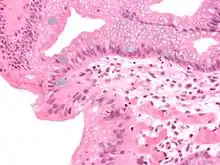

Both macroscopic (from endoscopy) and microscopic positive findings are required to make a diagnosis. Barrett's esophagus is marked by the presence of columnar epithelia in the lower esophagus, replacing the normal squamous cell epithelium—an example of metaplasia. The secretory columnar epithelium may be more able to withstand the erosive action of the gastric secretions; however, this metaplasia confers an increased risk of adenocarcinoma.[15]

Intestinal metaplasia

The presence of goblet cells, called intestinal metaplasia, is necessary to make a diagnosis of Barrett's esophagus. This frequently occurs in the presence of other metaplastic columnar cells, but only the presence of goblet cells is diagnostic. The metaplasia is grossly visible through a gastroscope, but biopsy specimens must be examined under a microscope to determine whether cells are gastric or colonic in nature. Colonic metaplasia is usually identified by finding goblet cells in the epithelium and is necessary for the true diagnosis.

Many histologic mimics of Barrett's esophagus are known (i.e. goblet cells occurring in the transitional epithelium of normal esophageal submucosal gland ducts, "pseudogoblet cells" in which abundant foveolar [gastric] type mucin simulates the acid mucin true goblet cells). Assessment of relationship to submucosal glands and transitional-type epithelium with examination of multiple levels through the tissue may allow the pathologist to reliably distinguish between goblet cells of submucosal gland ducts and true Barrett's esophagus (specialized columnar metaplasia). The histochemical stain Alcian blue pH 2.5 is also frequently used to distinguish true intestinal-type mucins from their histologic mimics. Recently, immunohistochemical analysis with antibodies to CDX-2 (specific for mid and hindgut intestinal derivation) has also been used to identify true intestinal-type metaplastic cells. The protein AGR2 is elevated in Barrett's esophagus[17] and can be used as a biomarker for distinguishing Barrett epithelium from normal esophageal epithelium.[18]

Epithelial dysplasia

After the initial diagnosis of Barrett's esophagus is rendered, affected persons undergo annual surveillance to detect changes that indicate higher risk to progression to cancer: development of epithelial dysplasia (or "intraepithelial neoplasia").[21] Among all metaplastic lesions, around 8% were associated with dysplasia. particularly a recent study demonstrated that dysplastic lesions were located mainly in the posterior wall of the Oesophagus.[22]